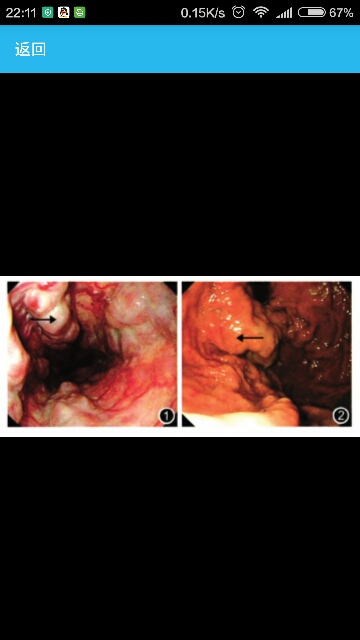

因“黑便10 d”入院。 患者无腹痛、腹胀、腹泻等症状,否认抗凝药物及毒物摄入史,无手术、出血及输血史,无异常出血家族病史。 临床表现体温37℃,脉搏85次/min,血压115/80 mm Hg(1 mm Hg=0.133 kPa),皮肤、巩膜无黄染,睑结膜中度苍白,可见肝掌及蜘蛛痣。腹部平坦,无腹壁静脉曲张,肝脾肋下未触及。 辅助检查RBC 2.71 x 1012/L,Hb 81 g/L,WBC 40×109/L,PLT 30 x 109/L,尿常规检查正常,大便潜血试验阳性。乙型病毒性肝炎标志物检测:HBsAg、抗-HBe、抗-HBc阳性。肝功能检查:ALT 44 U/L,AST 35 U/L,TBil 18.9 umol/L.Alb 28 g/L,PT 36.8 s,活化部分凝血酶时间(activated partial thromboplastin time,APTT)34.3 s,AFP 35 ug/L。患者PT明显延长,APTT正常,重复检测结果相似。上腹部CT检查示肝脏体积缩小,肝裂增宽,边缘变钝,脾肿大,食管胃底静脉侧支循环建立。胃镜检查示食管距门齿25 cm以下4条静脉呈串珠样改变,向下延伸至贲门,局部呈瘤样改变,可见多处交通支,红色征阳性,胃底可见静脉呈瘤样改变。结肠镜检查无异常。 经外周静脉直接采血,将患者血浆与普通血浆进行1:1混合血浆PT纠正试验,PT纠正为14.5 s。将患者血液标本送山东省血液中心,检测凝血因子Ⅶ的活性为5%(参考区间为50%~150%),凝血因子Ⅱ、Ⅷ、Ⅸ、X活性在正常范围。 诊断:先天性凝血因子Ⅶ缺乏症。 治疗患者入院后给予氨甲环酸等止血药物、静脉输注维生素K1,间断小剂量输注新鲜冰冻血浆治疗,出血停止,大便变黄,Hb浓度稳定。根据凝血因子Ⅶ的半衰期,拟术中输注新鲜冰冻血浆和PLT,备重组人凝血因子Ⅶa,若凝血功能障碍时静脉注射。 患者于2012年3月30日在全身麻醉下行贲门周围血管离断+脾切除术。手术前输注新鲜冰冻血浆200 ml和PLT16 U。患者术中无明显的凝血功能障碍表现,输注新鲜冰冻血浆400 ml,术野无异常出血。术中出血量约200 ml,未使用重组人凝血因子Ⅶa。术后患者恢复良好,腹腔引流管内引流淡红色液体,第1天引流300 ml,第2天引流100 ml,第3天引流20 ml后拔除引流管,术后8 d拆线切口甲级愈合,无出血,无血肿形成,患者治愈出院。出院1个月后随访,患者手术切口愈合良好。复查肝功能:转氨酶、胆红素浓度正常,Alb 30 g/L,PT 36.0 s,APTT 35.3 s。血常规:RBC 2.89×1012/L,Hb 83 g/L,WBC 40×109/L,PLT 450×109/L。